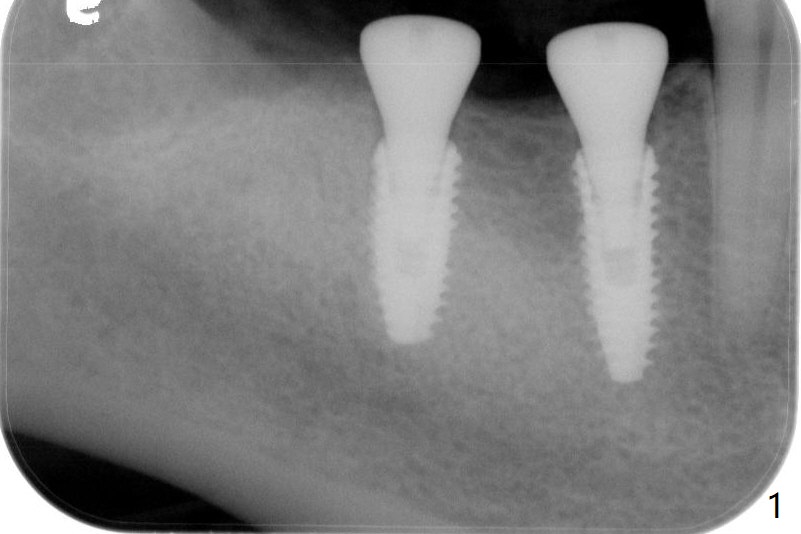

After infiltration and pdl anesthesia, the tooth #32 is extracted with elevators and forceps.  Drilling protocol per CBCT plan, no deviation (see instruction sheets). Implants are placed subcrestal: 4.0x11.5 mm at #30 and 4.5x10 mm #31 with >50 Ncm. Healing abutments (6x4 mm) are placed (Fig.1,2).  Resorbable suture is used to close #32 socket. Sensation returns. There is no hemorrhage.  Although the wound looks healing 4 days postop and the healing abutments have normal position (Fig.3), the patient complains of fair amount of pain.